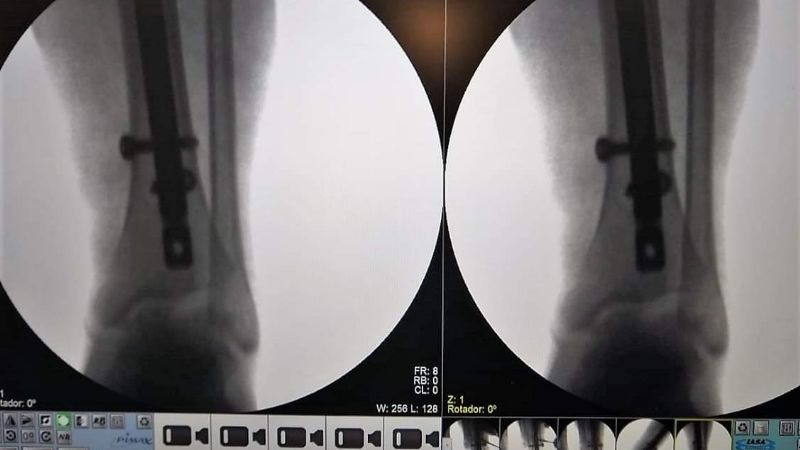

Esta intervención quirúrgica requirió la colocación de un clavo endomedular acerrojado de titanio en tibia.

Si bien se hacían muchos tipos de intervenciones quirúrgicas históricamente, este tipo de operaciones son posibles desde que el Hospital de Recreo cuenta con un Arco en C, aparato especializado en imágenes de Rayos X que permitió un salto de calidad en cirugías traumatológicas de mayor complejidad.

Hasta hace poco más de un año, las cirugías traumatológicas en Recreo eran más sencillas; las fracturas complejas debían ser derivadas a otros centros porque no se podía operar. Sin el Arco en C es imposible realizar estos procedimientos, porque el cirujano necesita tener una imagen en vivo para poder evaluar si el material está correctamente colocado.